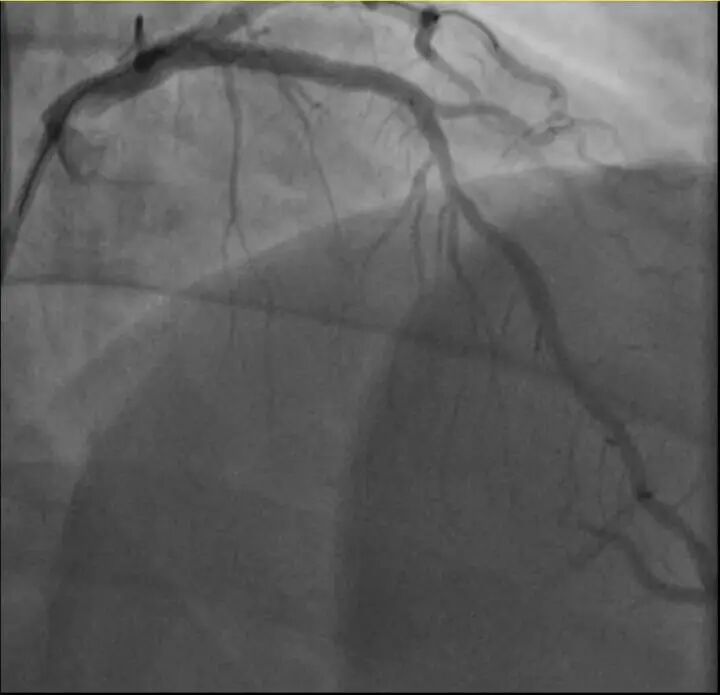

介入治疗前影像图

孙先生花了一年时间

体重从原来的96kg瘦到90kg

但让他没想到的是

意外还是来了

近日,他带孩子去练习羽毛球,没想到上场挥拍仅10分钟左右,就因心前区剧烈绞痛被送进了急诊。

浙江医院心血管内科的医生分析,剧烈运动导致这位患者心脏的不稳定斑块破裂,进而造成前降支近段次全闭塞。所幸送医及时,孙先生的身体险情被化解。